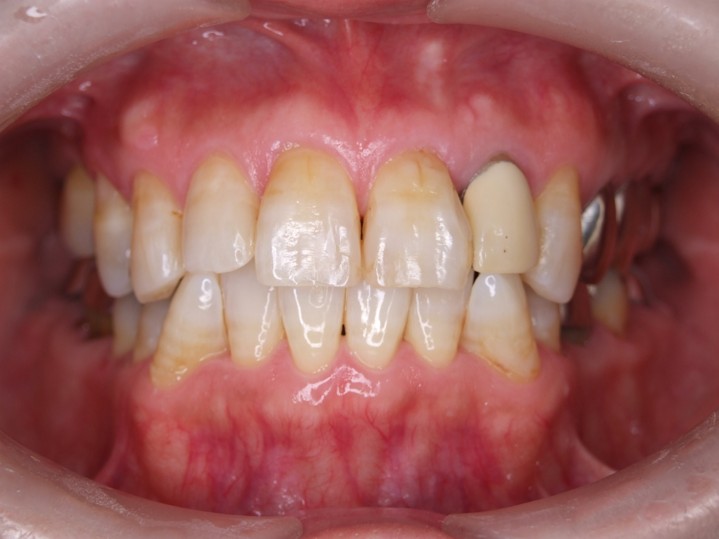

| 主訴 | 50代男性 右上の歯と歯茎が痛い。どこで噛んでいいのか分からないので夜も眠れない |

| 治療内容 | 外科矯正治療・インプラント治療・セラミック治療を行いました。 |

| 治療費 | 4,500,000円(税込み) |

| 治療期間 | 4年(矯正治療期間 3年) |

| 治療回数 | 60回 |

| 想定されたリスク | 顎骨の変形があったので、全身麻酔下による外科処置が必要になり、身体的、精神的負担が増す可能性がありました。 清掃状況によっては矯正中にむし歯が発生するリスクがありました。 |